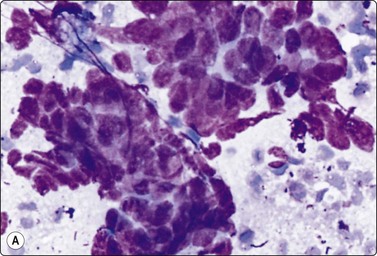

Embryonal carcinoma (Figs 13.33 and 13.34)14,58-61,63,65,66

image image

Fig. 13.33 Embryonal carcinoma

(A) Adenocarcinoma-like tissue fragment of large malignant cells with large vesicular nuclei, coarse chromatin, prominent nucleoli; prominent cytoplasmic vacuolation (MGG, HP); (B) Fragment of undifferentiated mesenchymal tissue right; cluster of malignant epithelial cells with large vesicular nuclei and prominent large nucleoli (H&E, HP) left.

image

Fig.13.34 Embryonal carcinoma

Tissue section corresponding to Fig. 13.33B (H&E, IP).

Criteria for diagnosis

Cell-rich smears,

Frequent three-dimensional clusters,

Occasional tendency to acinar and microglandular grouping,

Large vesicular, obviously malignant nuclei, large nucleoli,

Indistinct cell borders,

Basophilic to amphophilic, sometimes pale, vacuolated cytoplasm,

Immunocytochemistry: cells positive for PLAP, OCT 3/4, CD30, AE1/AE3 and CK7.

The vesicular nuclei of embryonal carcinoma are larger and more pleomorphic than those of seminoma, the chromatin is coarse and irregular and nucleoli are large, occasionally huge, and eosinophilic. The cytoplasm is pale and distinctly vacuolated, but not ‘bubbly’. It is not highly fragile and a TB as in seminoma is not seen. Cytoplasmic boundaries are poorly defined (Fig. 13.33). Hemorrhage and tumor necrosis may be prominent and may hamper the identification of diagnostic cells. It is usually not seen in smears of seminoma. Chromatin threads and reticulated material resembling TB can occur. Large syncytiotrophoblastic cells may be found. Prominent lymphoid/plasma cell infiltrates or mucus are not seen. The presence of cellular mesenchyme on its own does not warrant a designation of teratoma (Figs. 13.33B and 13.34).49